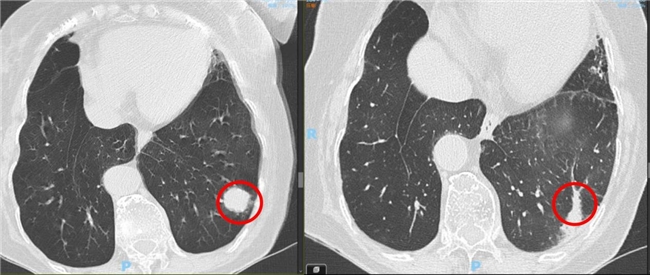

2022年,77岁的李女士(化名)确诊左肺下叶早期鳞癌。肿瘤虽属早期,但综合评估显示,其高龄状态使围手术期并发症风险增加。经医院多学科团队讨论,最终采纳了胡旭东主任的建议,采用SBRT作为根治手段。

治疗分5次进行,总剂量55Gy,在两周内完成。整个过程无需开胸麻醉,患者耐受良好。治疗后随访显示,肿瘤持续缩小并长期保持稳定。截至2025年8月,患者无疾病进展迹象,治疗相关反应轻微,生存质量得以提升。